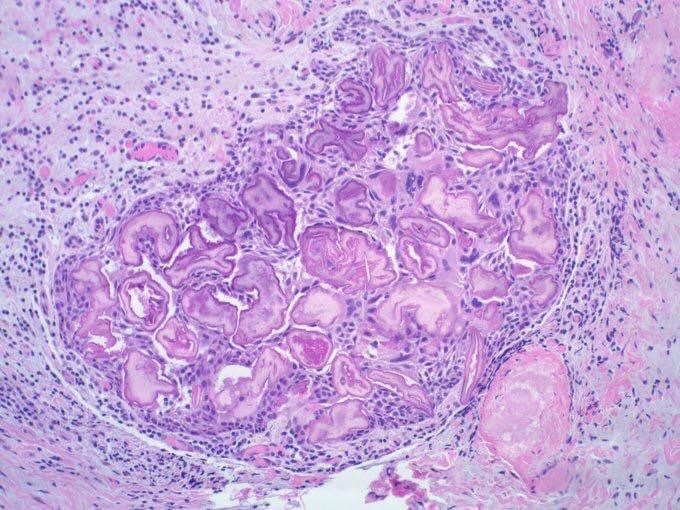

| Calcifying Odontogenic Cyst ( Gorlin Cyst, COC) |

basal cell reverse polarity  |

|||||

ghost cells (嗜酸無核)  |

| β catenine + | |||||